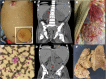

Mutations in the genes coding for cytokines, receptors, second messengers, and transcription factors of interferon gamma (IFN-γ) immunity cause Mendelian susceptibility to mycobacterial disease (MSMD). We report the case of a 7-year-old male patient with partial dominant (PD) IFN-γ receptor 1 deficiency who had suffered from multifocal osteomyelitis attributable to bacille Calmette-Guérin vaccination since the age of 18 months. He developed hemophagocytic lymphohistiocytosis (HLH), a hyper-inflammatory complication, and died with multiorgan dysfunction, despite having been diagnosed and treated relatively early. Patients with PD IFN-γR1 deficiency usually have good prognosis and might respond to human recombinant subcutaneous IFN-γ. Several monogenic congenital defects have been linked to HLH, a catastrophic "cytokine storm" that is usually ascribed to lymphocyte dysfunction and thought to be triggered by interferon gamma. This is the sixth patient with both MSMD and HLH of whom we are aware. The fact that patients with macrophages that cannot respond to IFN-γ still develop HLH, bring these assumptions into question.